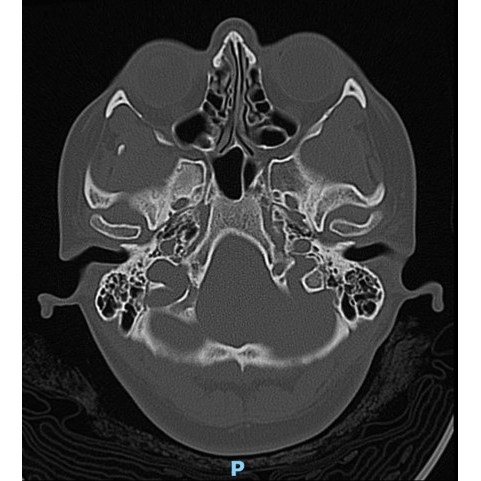

CT Head Case Photo #1 , CT Head/Neck Case Photo #2 , Brain MRI [Photo3] and CT Chest Case Photo #4 were all normal.